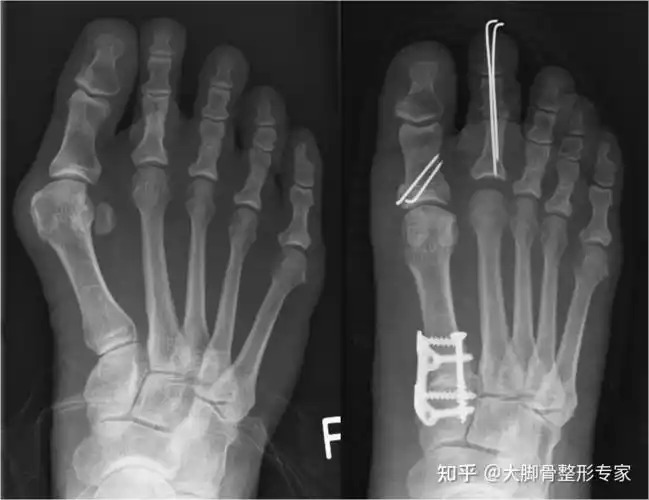

脚骨x光片术前术后对比在油管上查了很多关于拇外翻手术的视频(血腥

拇外翻大脚骨手术矫治术

大脚骨scarf akin截骨 - 好大夫在线